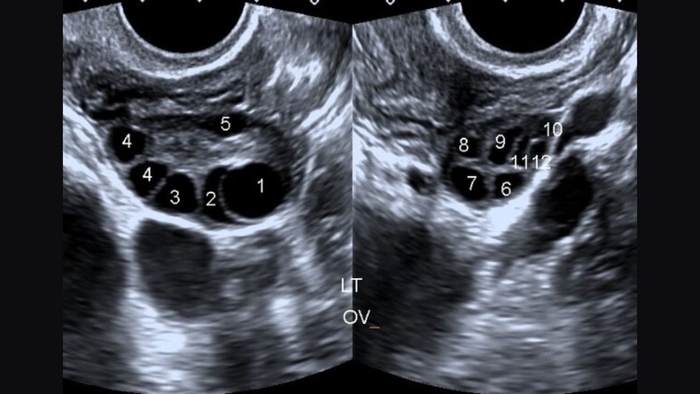

Siêu âm buồng trứng đa nang giúp bác sĩ quan sát trực tiếp cấu trúc của buồng trứng. Một số dấu hiệu đặc trưng có thể thấy được qua hình ảnh siêu âm bao gồm:

- Buồng trứng có nhiều nang nhỏ (từ 12 nang trở lên, mỗi nang có kích thước 2-9mm).

- Buồng trứng có kích thước lớn hơn bình thường.

- Nang xếp vòng quanh ngoại vi buồng trứng, hình ảnh còn được gọi là “vòng hoa”.

Dựa vào các đặc điểm này kết hợp với triệu chứng lâm sàng (kinh nguyệt không đều, rối loạn hormone…), bác sĩ sẽ đưa ra chẩn đoán chính xác về tình trạng PCOS của bệnh nhân.